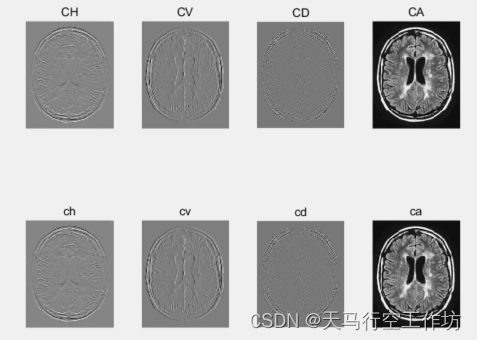

一层小波分解,低频采用邻域加权方差融合,高频采用基于局部梯度信息的融合算法

[CA,CH,CV,CD]=dwt2(X,'haar');%一层小波分解二维图像信号

[ca,ch,cv,cd]=dwt2(Y,'haar');